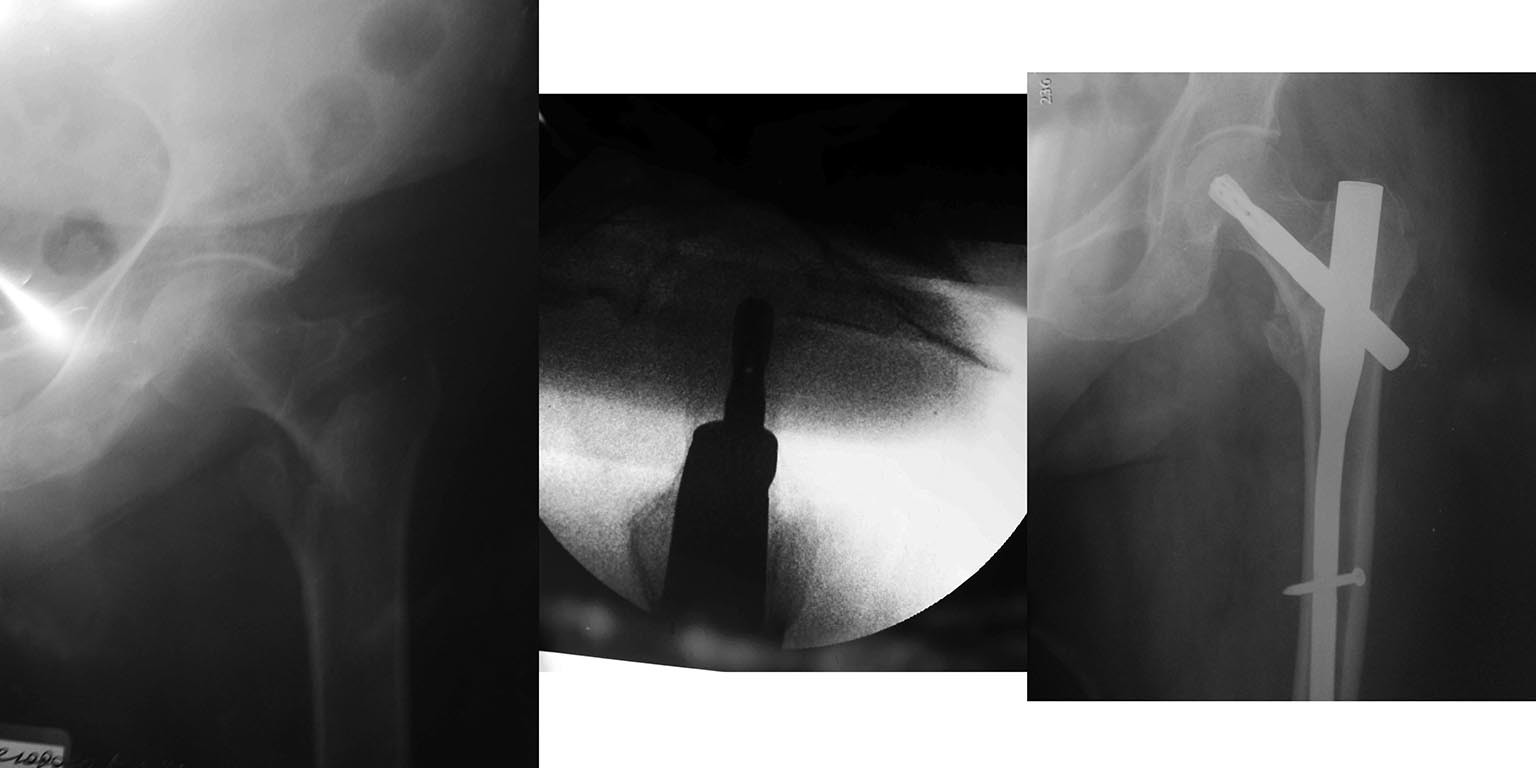

Перелом шейки левой бедренной кости у пациентки 1940 года рождения.Женщина без серьёзной сопутствующей патологии. Операция БИОС перелома шейки бедра через 5 суток после травмы стержнем PFNa synthes.

Одно но- имеется чрезвертельный перелом, шейка целая. Нагрузка 30 процентов с первых дней.

2. Перелом чрезвертельный

3. репозиция хорошая, синтез то же.

Как коллеги уже поправили, это не перелом шейки бедра, а чрезвертельный. Вообще, остеосинтез современными имплантатами при таких переломах предполагает неограниченную нагрузку сразу. Но здесь немного коротковат шеечный винт (helical blade). Так что совет подождать с полной нагрузкой вполне уместен. То есть вес ноги или процентов 25-30, а полную нагрузку - месяцев с двух.

Здесь можно рарешать полную нагрузку с первых дней, ограниченную лишь комфортом больной (некоторые больные жалуются на боли в коленном суставе на больной стороне, возможно связанные с невосстановленным тонусом мышц бедра). Касательно длины длины спирального лезвия - судя по снимкам, TAD=20мм, так что Баумгартнер бы не придрался. Кстати, некоторые более поздние авторы рекомендуют TAD 20-30 мм (http://www.josr-online.com/content/8/1/35).